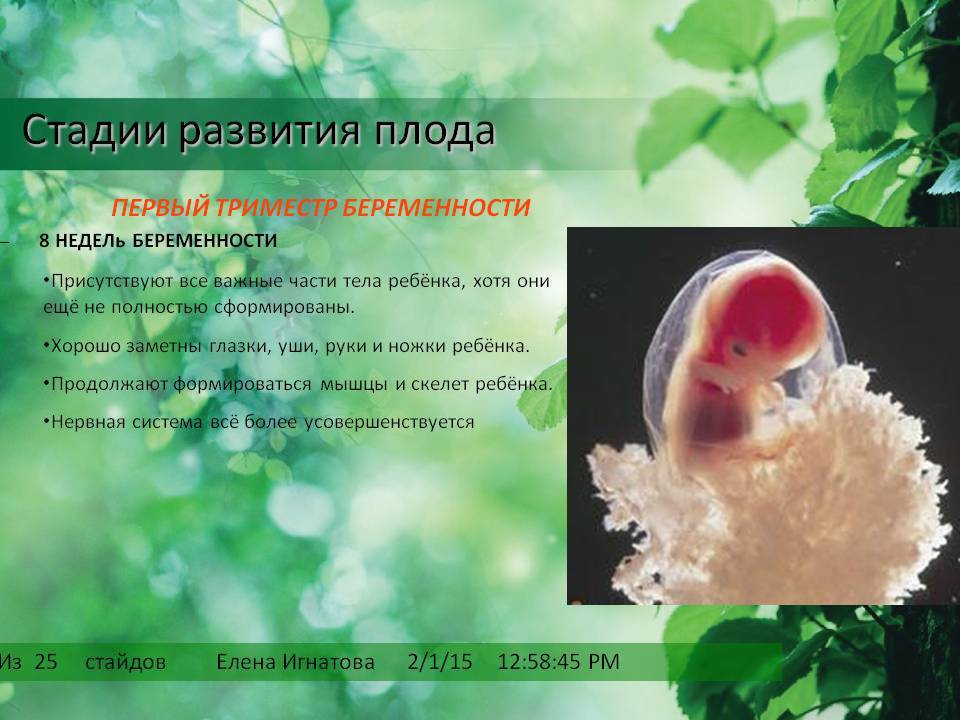

Формирование Плода в Первом Триместре: Важные Этапы